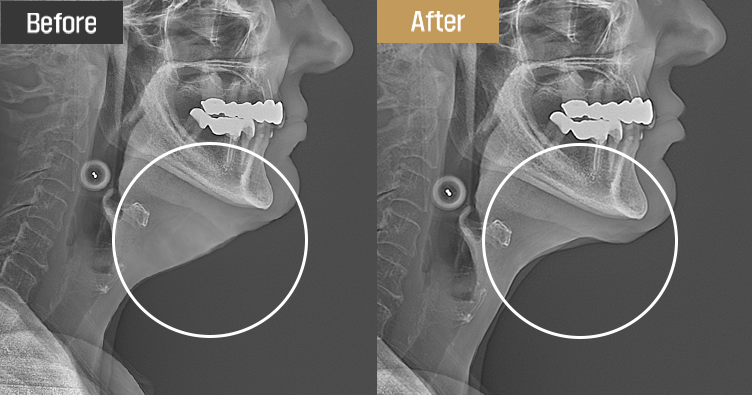

Personalized design through precise diagnosis

Drawing on our extensive anatomical knowledge, we develop a customized plan for each patient

using X-rays and facial ultrasound. By carefully evaluating fat thickness, skin sagging, muscle laxity,

and salivary gland enlargement, we ensure safe and reliable results.

Patients can immediately verify the effects with an X-ray right after surgery.

Visible results you can see for yourself

The results can be seen instantly with an X-ray following surgery.